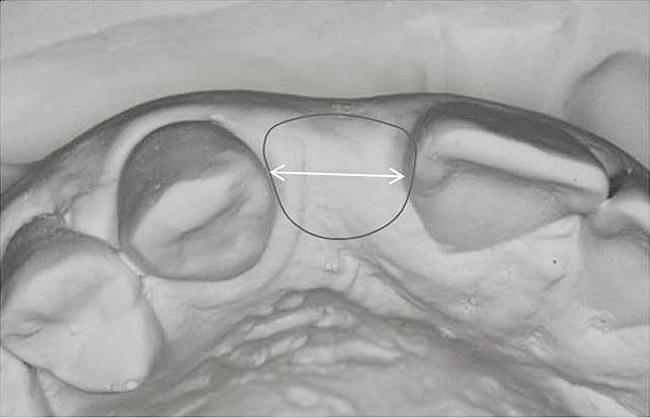

Figure 14   Exploiting study casts for planning single-tooth implant placement and restoration: Mounted study casts permit an estimation of available bone volume (Fig 13); measure the bound edentulous space inter-tooth dimensions (Fig 14); measure the available inter-arch dimension (restorative space) (Fig 15); and evaluate alveolar ridge/tooth relationships (distance from zenith represented by plastic stent to ridge crest) (Fig 16).

Figure 14